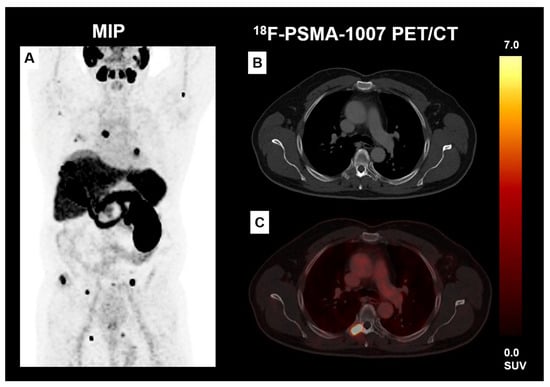

- Mittlmeier, L.M.; Unterrainer, M.; Rodler, S.; Todica, A.; Albert, N.; Burgard, C.; Cyran, C.; Kunz, W.; Ricke, J.; Bartenstein, P. 18F-PSMA-1007 PET/CT for response assessment in patients with metastatic renal cell carcinoma undergoing tyrosine kinase or checkpoint inhibitor therapy: Preliminary results. Eur. J. Nucl. Med. Mol. Imaging 2021, 48, 2031–2037. [Google Scholar] [CrossRef] [PubMed]